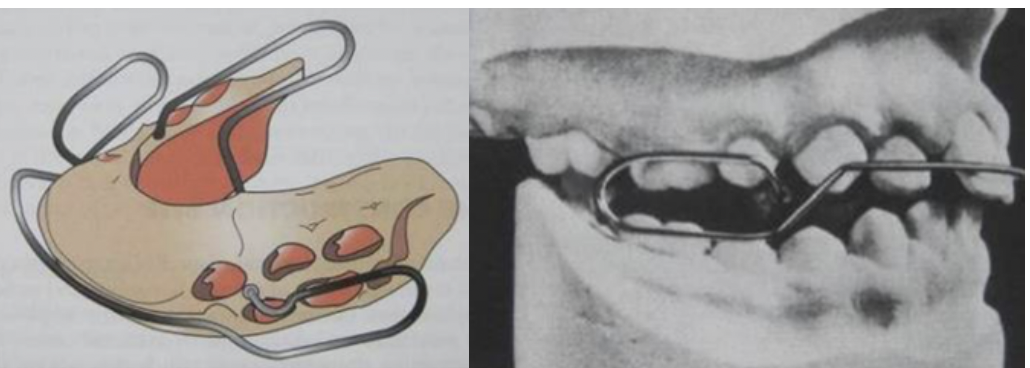

Herbst appliance

- 唯一固定式functional appliance

- 推開上顎第一大臼齒、下顎第二乳臼齒,下顎往前